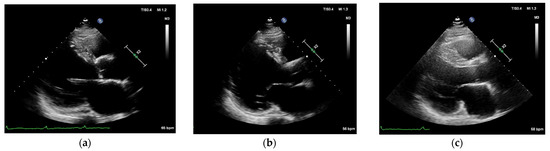

2. Case Reports